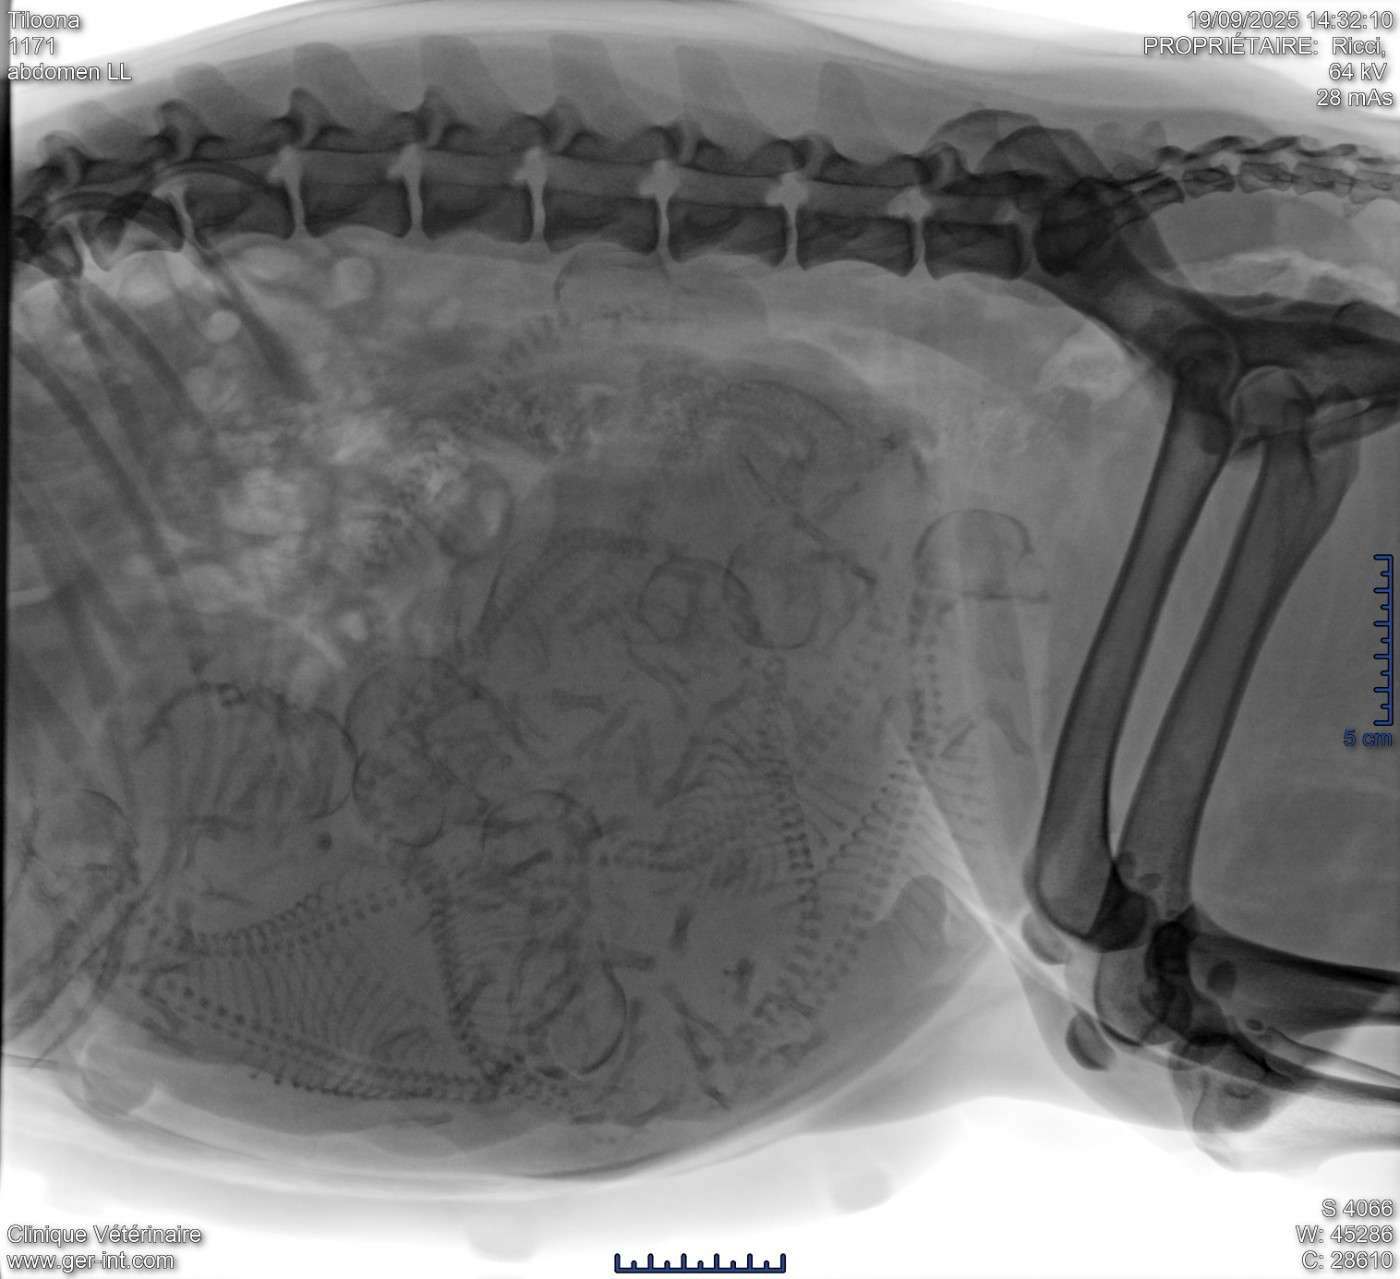

Bébés Tiloona 2025